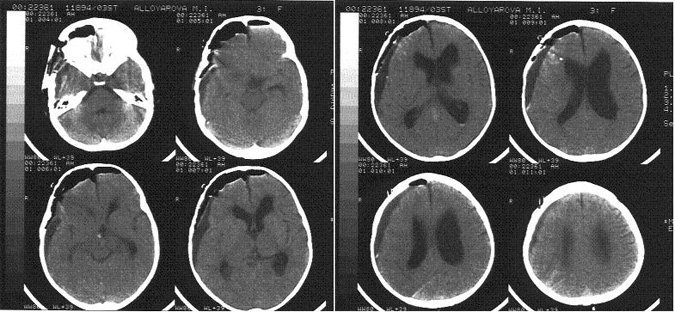

При компьютерно-томографическом (КТ) исследовании головного мозга (рисунок 1) выявлялось скопление воздуха и ликвора в субдуральном пространстве, преимущественно справа. Правый боковой желудочек копремирован. Опухоль удалена радикально. При транскраниальном допплерографическом исследовании данных за вазоспазм не было.

В 3 сутки была снижена доза дексаметазона до 2 мг/сут, гидрокортизон и Л-тироксин в прежней дозе, минирин введен 1 раз в дозе 1 мг.4 сутки после операции. Состояние больной ухудшилось, отмечалось нарушение сознания до сопора - комы, остро развился генерализованный судорожный припадок: клонические сокращения мимической мускулатуры левой половины лица, тризм жевательной мускулатуры, тонические судороги в конечностях по типу децеребрации. При КТ исследовании головного мозга было выявлено (рисунок 2): равномерное скопление ликвора субдурально с обеих сторон, уменьшение размеров желудочковой системы по сравнению с 1 сутками. В течение суток отмечалось еще 4 генерализованных судорожных припадка. Выявлялась устойчивая гипертермия до 39ºС.